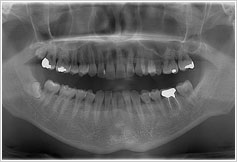

その上で、お口の中の状態を把握するためにレントゲン写真を用いて、ご希望を最大限に叶えるために、どのような治療方法があるのかをご相談させていただきます。

噛み合わせの検査、歯周病検査、レントゲン診査、CT撮影など、患者様の状況に合わせて、必要な検査を選択し、より詳しい状態を把握します。